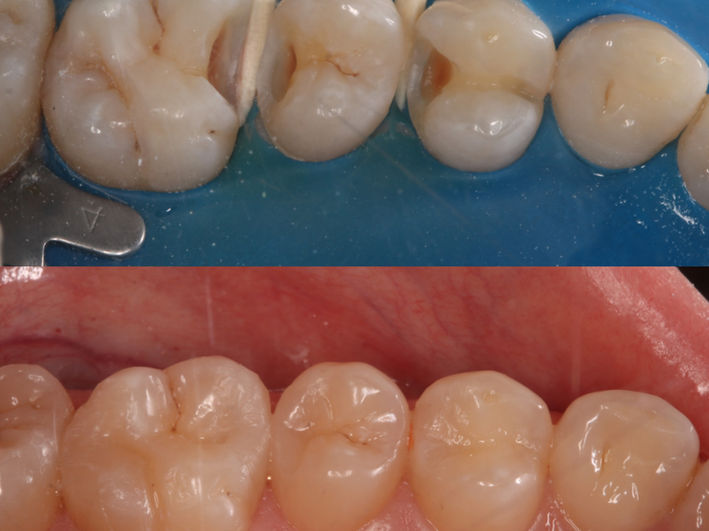

4. Onlay

Onlayul este o restaurare dentară utilizată pentru a repara o zonă afectată de carie sau o structură dentară deteriorată, care nu necesită o coroană completă. Onlay-urile sunt realizate din materiale durabile, cum ar fi compozitele sau ceramica și se aplică pe suprafața masticatorie a dintelui, oferind suport și stabilitate.

Pacienta se prezinta în cabinet pentru a trata leziunea de la nivelul molarului inferior. Analizând ocluzia observăm absența spațiului suficient pentru o lucrare corectă. Astfel, am aplicat un aparat dentar local cu mini-implanturi pentru a intruza molarul superior si a recâștiga spațiul necesar.

După tratamentul ortodontic și câștigarea spațiului necesar am preparat minim dintele, am luat amprentă și tehnicianul a realizat un onlay din material compozit. Acesta a fost lipit sub izolare cu digă.